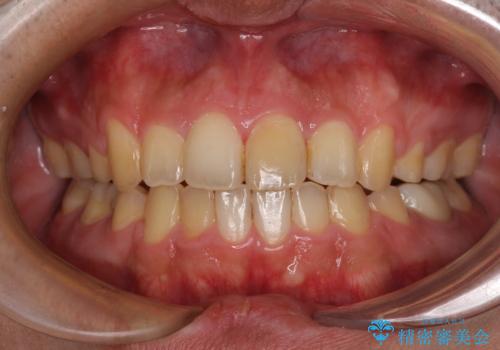

歯冠長延長術を行ったことで、自然な形態かつ清掃性の高いセラミッククラウンを装着することができました。

全顎的に治療を行ったため、治療期間も費用も負担は大きくなりましたが、統一感のある仕上がりとなりました。